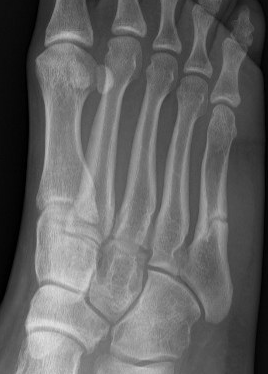

Xray

Zone 2 fractures

Union of zone 2 fracture with nonoperative care